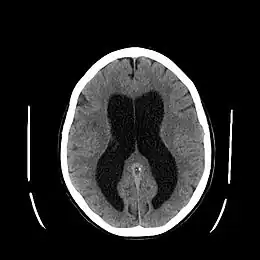

- Le scanner cérébral (sans injection d'iode) retrouve une dilatation quadriventriculaire sans élargissement des sillons corticaux sur l'ensemble de la convexité corticale et un arrondissement des angles latéraux des ventricules (ce qui permet de différencier hydrocéphalie et atrophie cérébrale).

- L'IRM cranioencéphalique est devenu l'examen de référence. Il permet de mettre en évidence la dilatation des ventricules et des anomalies périventriculaires